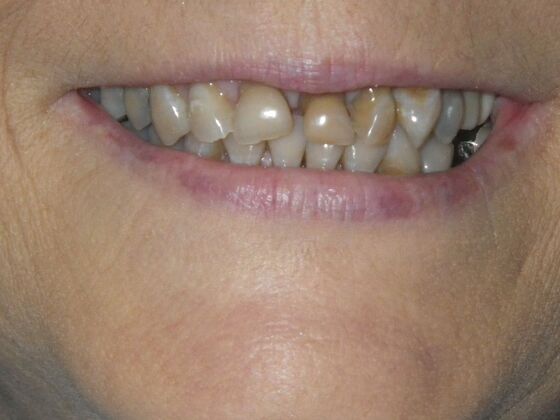

Cosmetic Changes with Veneers and Crown and Bridge: Case 6

Description

This patient had long term acidic erosion of upper and lower teeth eventually leading to loss of upper left central and lateral incisors. While she was somewhat happy with replacement of her front teeth with a removable appliance, she really desired to have something she didn't have to remove. So patient opted to be conservative with two single unit crowns as well as a four unit anterior bridge. These were fabricated using all ceramic without metal